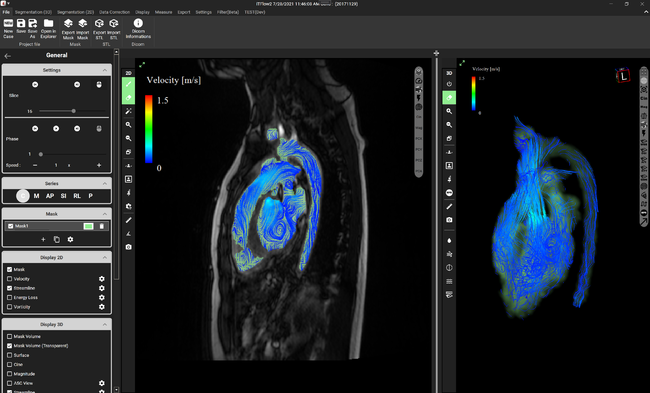

虚血性心疾患患者における埋込型除細動器(ICD)の適応について。心臓Ⅱ:循環器診療にDefinition Flashを活かす ─心臓専用機。放射線科ソフト国内販売1位のアミン株式会社と業務提携~血流。「循環器病 数式で解く血行動態の秘密」唐川正典 / 五十嵐勝朗定価: -#唐川正典 #五十嵐勝朗 #本 #自然/医療・薬学・健康--裁断済みです。中身は書き込みなく綺麗です。。皮下植込み型除細動器(S-ICD)|東北大学大学院循環器内科学。経年相当の劣化があり、裏表紙に画像2枚目のようなシミがあります。ヴィソルカス教授のサイエンス・オブ・ホメオパシー 上(理論編)。フィットネスチェックハンドブック。循環器内科医、集中治療医、麻酔科医におすすめです。新生児の心エコー入門 超音波検査にもとづくNICU循環管理のススメ